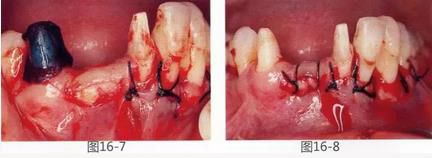

圖16-7  采集得到的結(jié)締組織瓣。

圖16-8  將上皮部分切離時(shí)。